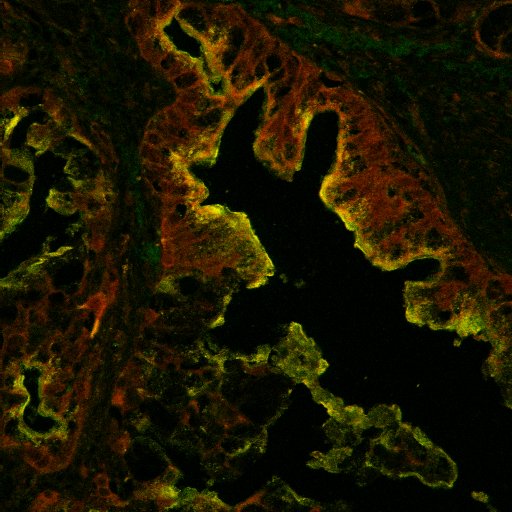

예술적인 현미경 사진이라면 요즘 보통 이런걸 얘기하곤 하죠,confocal microscopy 로 검색하시면 찾으실 수 있습니다.

아래 사진도 구글에서 제가 찾은 것입니다, 물론 이렇게 나오는 건 드뭅니다. 아마 이사진도 시약회사쪽에서 찍은 광고용 사진중 일부일겁니다.

아마도 기관지 상피 세포를 찍은 것 같은데 푸른색은 세포핵, 붉은 색은 세포끝에 붙어있는 섬모(cillia), 그리고 초록색은 세포질과 세포 뿌리에 해당하는 부분입니다.

보통 green-red 조합이 contrast 가 잘되기 때문에 두가지 조합을 가장 많이 사용합니다.

이론상으로는 5가지 이상 조합이 가능하지만 보통 2-3가지 색조합을 많이 사용합니다.

세포나 조직 항원에 눈으로 볼 수 있는 발색제를 붙여서 현미경으로 관찰해서 볼 수 있는 사진인데 형광 발색제를 쓰게 되면 이런 사진을 찍을 수 있습니다.